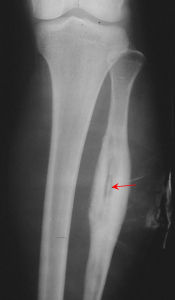

3.放射學變化:早期有蟲蝕狀骨破壞與骨質稀疏,並出現硬化區。有層狀骨膜反應,新生骨逐漸變厚和緻密,壞死脫落成為死骨。X線片上死骨表現為完全孤立的骨片,沒有骨小梁結構,濃白緻密,邊緣不規則,周圍有空隙。CT片可以顯示出膿腔與小型死骨。部分病例可經竇道插管造影顯示膿腔。

根據病史和臨床表現,特別是有經竇道及經竇道排出過死骨的,很容易診斷。X線片可以證實有無死骨,了解形狀、數量、大小和部位。以及附近包殼生長情況。一般不需要作CT檢查。

X線檢查:急性血源性骨髓炎早期無明顯變化,發病後3周左右可有骨質脫鈣、破壞,少量骨膜增生,以及軟組織腫脹陰影等。